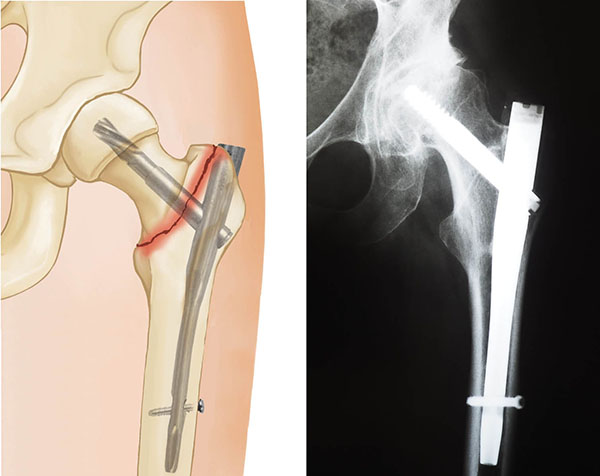

Intertrochanteric fractures are treated surgically with either a sliding compression hip screw and side plate or an intramedullary nail.

The intramedullary nail is placed directly into the marrow canal of the bone through an opening made at the top of the greater trochanter. One or multiple screws are then placed through the nail and into the femoral head. An additional screw is placed into the bone to control rotation.

hip fracture treated with intramedullary nail

Two-part intertrochanteric fracture treated with an intramedullary nail.

X-ray courtesy of Stuart J. Fischer, MD, FAAOS